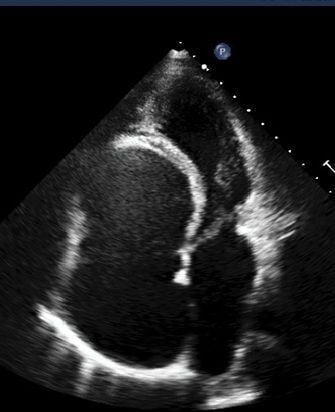

As the population of adult congenital heart disease (ACHD) survivors continues to grow, our committee addresses the unique complexities of their lifelong clinical management. We provide a dedicated platform for advancing specialized imaging standards and multidisciplinary care tailored to these unique anatomical challenges. By focusing on long-term follow-up and expert training, we ensure high-quality outcomes for patients transitioning into adult services. Join us in evolving the diagnostic tools and research necessary to support this rapidly expanding patient community.